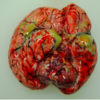

What is this image depicted of the female reproductive tract [1]

Endometriosis